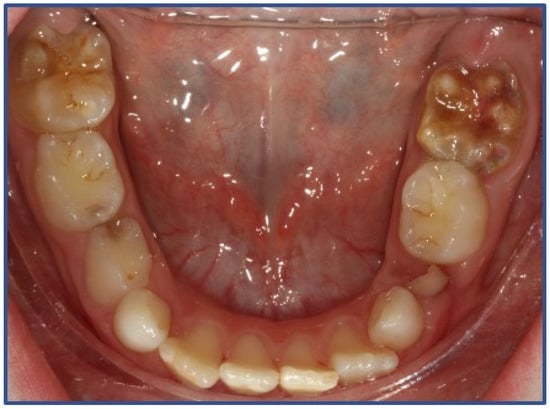

2. Materials and Methods

3. Results